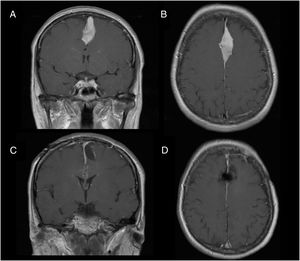

Illustrative case reportsPatient 1Our first patient was a 48-year-old woman with history of parasagittal meningioma; she had undergone surgery 10 years previously and subsequently presented tumour recurrence (Fig. 1A and B). The lesion was completely resected (Fig. 1C and D). After the procedure, the patient presented global aphasia and right hemiparesis (muscle strength 2/5). After a week receiving physical rehabilitation and speech therapy, she recovered strength in the right arm (5/5) and leg (4/5). Dysphasia resolved on day 6. Three weeks after the intervention, the patient was able to walk independently and had resumed work (modified Rankin Scale score of 0); she displayed 5/5 strength in all muscle groups.